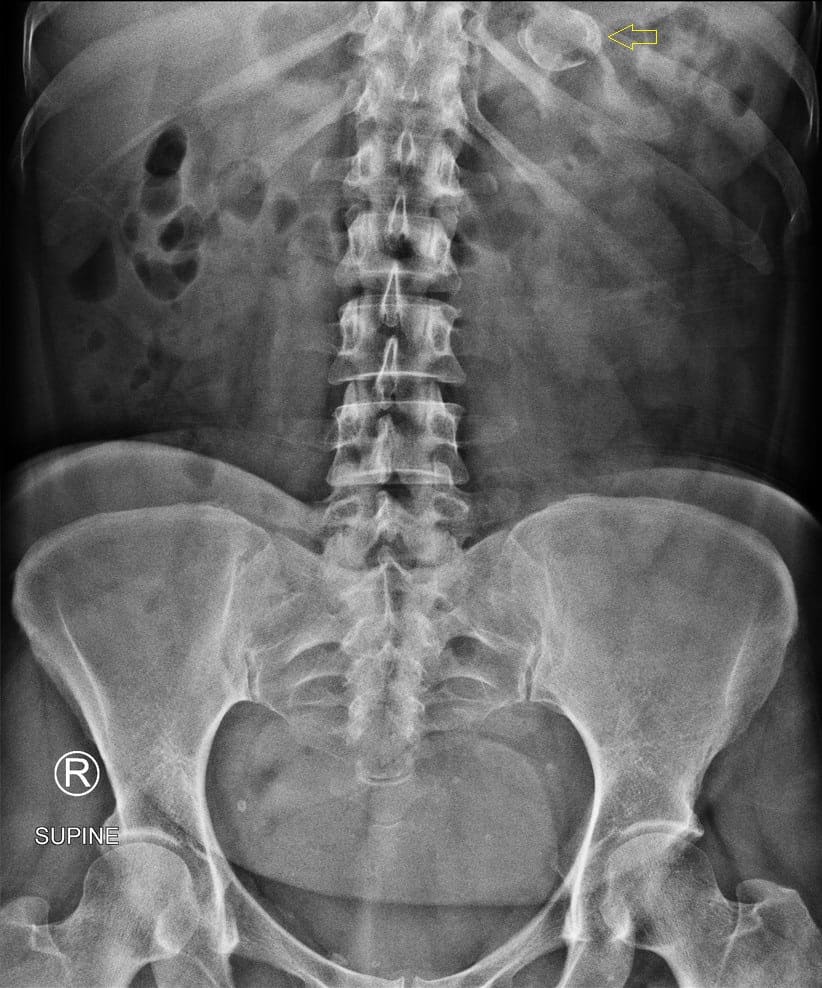

Phình ĐM lách (Sao chép) - BỆNH TIM MẠCH